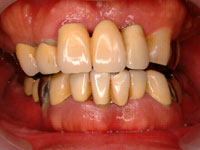

服用から1週間後。腫れた歯茎はピンク色に変化し、急性症状は治まっています。